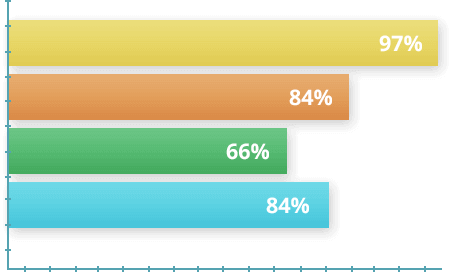

Independent studies have demonstrated the effectiveness of Glycopezil.

In 2024, studies were conducted with 1700 volunteers with varying degrees of diabetes. Depending on their individual conditions, participants used GlycoPezil for 30 days. At the end of the experiment, statistics were compiled based on the data obtained.

- 97% reduced glucose levels in air in 30 days.

- 84% improved energy and reduced fatigue

- 66% reduced the need for medication (under medical supervision).

- 81% control their sugar levels.

96% of endocrinologists recommend GlycoPezil